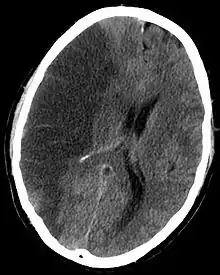

သင်(သို့မဟုတ်) တစ်စုံတစ်ယောက် လေဖြတ်ရောဂါ လက္ခဏာများကို ခံစားရပါက အချိန်နှင့်တစ်ပြေးညီ အလျင်အမြန် ကုသမှု ခံယူရန် အရေးကြီးပါသည်။ ကျွမ်းကျင်သော ဆရာဝန်၊ သူနာပြု၊ အကြောအဆစ် ပြန်လည်သန်စွမ်းရေး ကျွမ်းကျင်သူများရှိသော လေဖြတ်ရောဂါ အထူးကုဌာန(သို့မဟုတ်) ဆေးရုံသို့ အမြန်ဆုံး သွားရောက်၍ ကုသမှု ခံယူသင့်ပါသည်။ ရောဂါလက္ခဏာများ မိနစ်ပိုင်းအတွင်း သက်သာသွားသည့်တိုင် နီးစပ်ရာ ဆေးရုံဆေးခန်းသို့ သွားရောက်ပြသရန် လိုအပ်ပါသည်။ သို့မှသာ အကြီးစား လေဖြတ်ခြင်း မဖြစ်အောင် ကာကွယ်နိုင်မည် ဖြစ်ပါသည်။ ဆေးရုံတွင် ရှိနေစဉ် လေဖြတ်သည့် အကြောင်းအရင်းကို ရှာဖွေရန်လိုအပ်ပါသည်။ ဦးနှောက် ကွန်ပျူတာ ဓာတ်မှန်ရိုက်ခြင်း၊ သွေးစစ်ဆေးခြင်း၊ နှလုံးစမ်းသပ်စစ်ဆေးခြင်းများကို လိုအပ်သလို စမ်းသပ်စစ်ဆေးရမည်။ အဘယ့်ကြောင့်ဆိုသော် လေဖြတ်သည့် အကြောင်းအရင်းပေါ် မူတည်၍ ကုသပုံ ကွဲပြားနိုင်ပါသည်။ ဥပမာ-ဦးနှောက်သွေးကြောပိတ်၍ လေဖြတ်လျှင် သွေးကျဲဆေး၊ သွေးခဲပျော်ဆေးပေးရပြီး၊ ဦးနှောက်သွေးကြောပေါက်၍ လေဖြတ်လျှင် သွေးယိုစီးစေသည့် အကြောင်းအရင်းကို ရှာဖွေကုသ၍ လိုအပ်ပါက ခွဲစိပ်ကုသမှု ခံယူရပါသည်။ ရောဂါကြောင့် သန်စွမ်းမှု ပုံမှန်မရှိတော့သည့် ကြွက်သားများအတွက် ပြန်လည်သန်စွမ်းလာအောင် လေ့ကျင့်ခန်းများ ပြုလုပ်ပေးရန် လိုအပ်ပါသည်။ ကမ္ဘာပေါ်တွင် လေဖြတ်ရောဂါသည် လူများ မသန်မစွမ်းဖြစ်စေသော အဓိက အကြောင်းအရင်းတစ်ခု ဖြစ်ပါသည်။ လေဖြတ်ထားသော လူနာများသည် သင့်တင့်လျောက်ပတ်သော ရေရည်ပံ့ပိုးပြုစုစောင့်ရှောက်မှု လိုအပ်ပါသည်။ လေဖြတ်လူနာများ၏ ကိုယ်ခန္ဓာပြန်လည်သန်စွမ်းရေးအတွက် ကိုယ်ကာယပြန်လည်လေ့ကျင့်ပေးရေးသည် အလွန်အရေးပါ ပါသည်။ ယင်းသို့ လေ့ကျင့်ခြင်းကို လေဖြတ်ပြီးပြီးချင်း စတင်ပါက လူနာများအတွက် များစွာအကျိုးရှိပြီး တိုးတက်မှုလည်း မြန်စေပါသည်။ လေဖြတ်လူနာများသည် စိတ်ပိုင်းဆိုင်ရာ ဝေဒနာများလည်း ခံစားနိုင်ရပါသည်။ ၎င်းလူနာများ၏ စိတ်ပိုင်းဆိုင်ရာနှင့် ဘဝအရည်အသွေးမြင့်မားစေရန်အတွက် မိသားစု၊ မိတ်ဆွေ အသိုင်းအဝိုင်းနှင့် ကျန်းမာရေးဝန်ထမ်းများ၏ အားပေးကူညီမှု အမြဲရရှိရန် လိုအပ်ပါသည်။ လေဖြတ်ရောဂါ တစ်ကြိမ်ဖြစ်ဖူးသော လူနာများသည် မဖြစ်ဖူးသေးသော သာမန်လူနှင့် ယှဉ်ပါက နောက်တစ်ကြိမ် လေဖြတ်ရန် အခွင့်အလမ်း ပိုမိုများပါသည်။ သို့ဖြစ်၍ ၎င်းလူနာများအနေနှင့် လေဖြတ်စေနိုင်သော အကြောင်းအရင်းများကို ထိရောက်စွာ ကုသနိုင်ရန်၊ ကျန်းမာရေးအသိနှင့် ယှဉ်ကာ နေထိုင်မှုပုံစံတို့ကို လိုက်နာရန်၊ တတ်ကျွမ်းနားလည်သော ကျန်းမာရေး ဝန်ထမ်းများ၏ ပုံမှန်စောင့်ရှောက်မှုခံယူရန် အရေးကြီးပါသည်။ နောက်တစ်ကြိမ် လေထပ်မဖြတ်ရန် ကာကွယ်မှုများ ပြုလုပ်သင့်ပါသည်။ လေဖြတ်ရောဂါသည် ကာကွယ်နိုင်သော ရောဂါတစ်ခု ဖြစ်ပါသည်။ လေဖြတ်ခြင်းကို ဖြစ်စေသော အကြောင်းတရားများကို သိရှိထားခြင်း၊ ရောဂါကာကွယ်ခြင်း၊ ကျန်းမာအောင် နေထိုင်ခြင်းပြုလုပ်ရန် လိုအပ်ပါသည်။ ရောဂါများရှိလျှင်လည်း စနစ်တကျ ဆေးကုသမှု ခံယူးထားပါက လေဖြတ်ရန် အခွင့်အလမ်းများစွာ လျော့ကျသွားနိုင်ပါသည်။